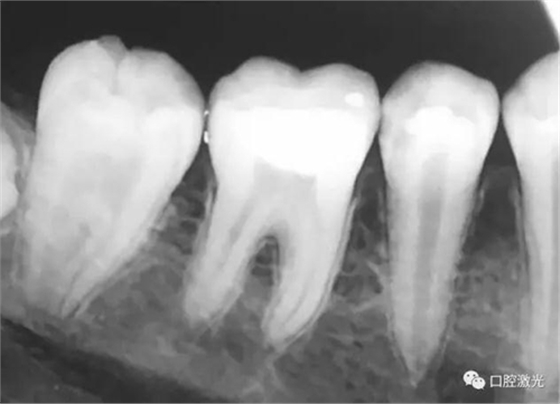

活髓理療治療結果令人滿意,沒有出血,也沒有出現(xiàn)碳化。患者沒有感受到不適并表示滿意。為了跟蹤激光輔助活髓切除術的治療效果,手術完成即刻和5周后分別拍攝了X光圖像。5周后的牙髓活性溫度測試也顯示陽性。

治療后即刻